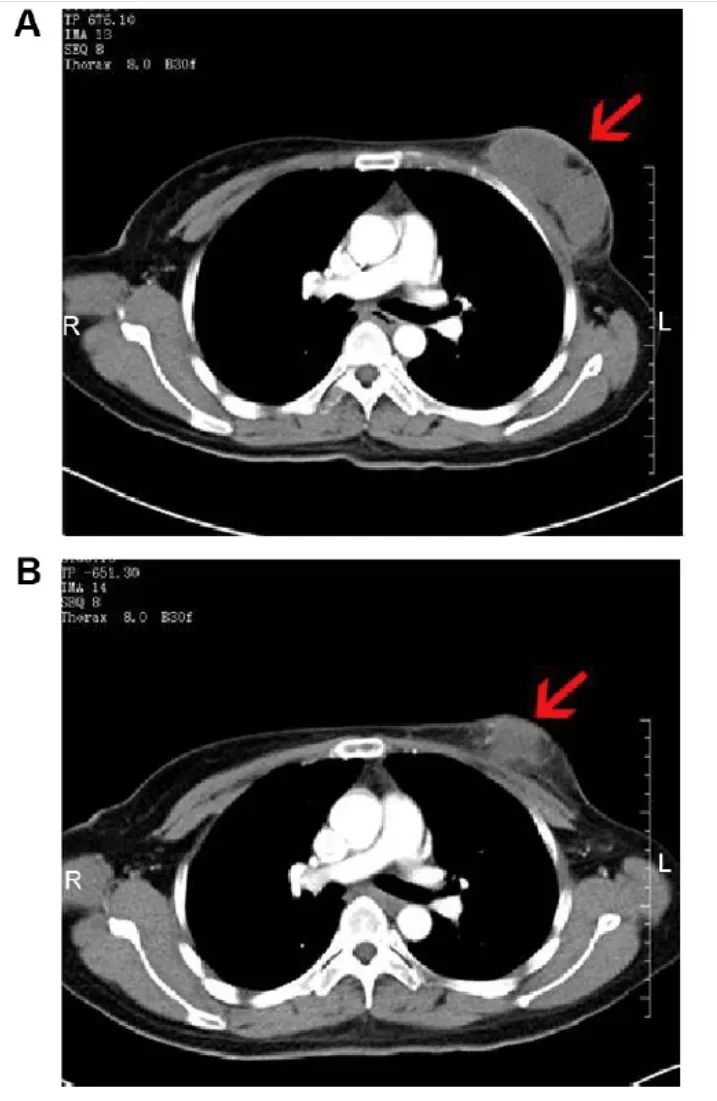

暨南大学研究团队开展的NK细胞治疗复发性乳腺癌临床研究(NCT02853903)中,共纳入36例病理确诊的复发性乳腺癌患者,其中一位46岁患者的显著疗效引发关注。

该患者治疗前后的影像学变化尤为典型:治疗前CT扫描显示,其右乳存在8.0×3.8×5.7cm的软组织肿块,边界模糊,增强CT呈中度不均匀强化;腋窝可见多处肿大淋巴结,最大者约2.9×1.7×3.8cm(详见下图A)。经NK细胞治疗2个月后,影像学复查显示肿块缩小至6.8×3.5×5.8cm,强化程度减弱为轻度不均匀;腋窝肿大淋巴结亦显著缩小(详见下图B),展现出NK细胞疗法在复发性乳腺癌中的潜在抗肿瘤活性。

▲图源“Dovepress”,版权归原作者所有,如无意中侵犯了知识产权,请联系我们删除